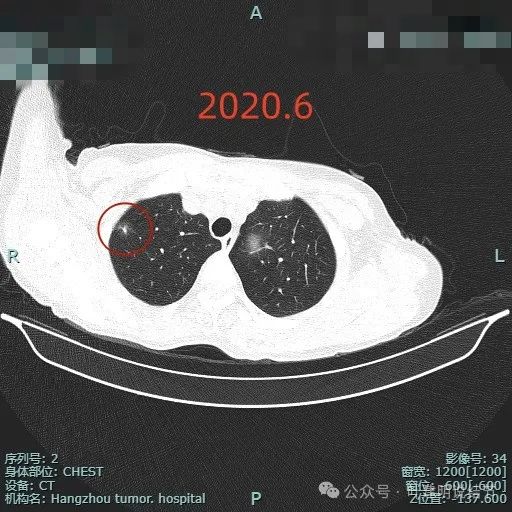

2020年时开始发现有出现明显实性成分,整体轮廓较清,但瘤肺边界稍糊,病灶仍较小,邻近胸膜没有明显牵拉凹陷。